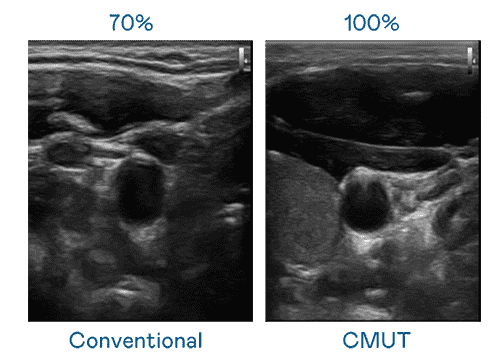

CMUT 技术是一种用电容式微机电元件来产生超音波讯号的技术。。与传统 PZT 压电式技术相比,,CMUT 频宽增加 30%,,,更宽频的超音波讯号让影像解析度大幅提升,,,,是实现高影像品质医疗超音波扫描、、促进精准医疗发展的关键技术。。。

大频宽带来超清晰影像

超音波影像的解析度高低,,首先取决于探头能发出的讯号频宽。。尊龙z6 CMUT 可提供高清晰的超音波讯号,,,,提供高频宽、、、、高灵敏度、、、影像纹理细节更高的超音波影像,,协助医护人员缩短影像判读时间及利用精准的医疗影像进行诊断。。。。